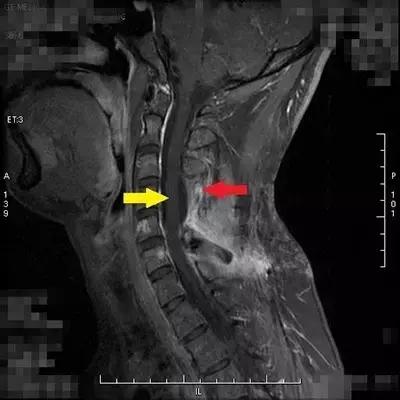

患者小康(化名)今年26岁,2013年查出椎管内肿瘤并进行切除,2015年12月复发到北京清华长庚医院就诊,经神经外科医师评估后再次行切除术,病理报告为间变型血管周细胞瘤。术后三个月复查,核磁共振扫描提示:C5-C6(“C”代表颈椎)水平椎管内硬膜外左侧及C5/6左侧椎间孔区仍可见实性强化影,考虑为肿瘤病变,建议行术后放射治疗。